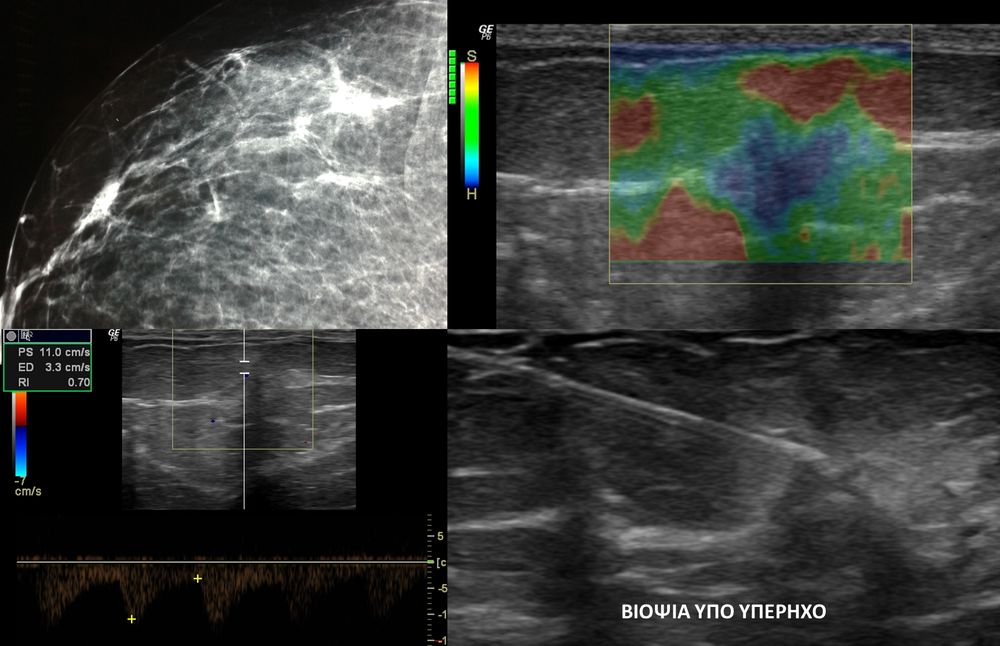

Η ελαστογραφία μαστού είναι μια σύγχρονη υπερηχογραφική μέθοδος που επιτρέπει τη διάκρισητων καλοήθων ογκιδίων από τους κακοήθεις όγκους.

Συνοπτικά ασκείται μια μικρή πίεση στους εντοπισμένους όγκους, μετρώντας την ελαστικότητα τους.

Ο καρκίνος γενικά εμφανίζει μεγαλύτερη σκληρότητα-ελαττωμένη ελαστικότητα σε σχέση με τα καλοήθη ογκίδια και επομένως η ελαστογραφία μπορεί να δώσει τις αναγκαίες πληροφορίες έτσι ώστε να μειώσει τις βιοψίες μαστού μόνο στις απολύτως απαραίτητες.